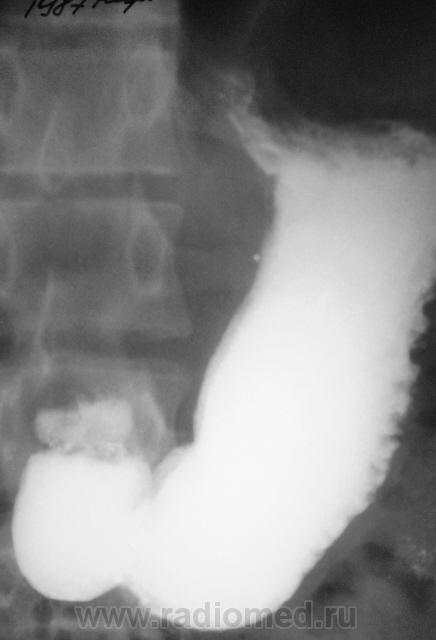

Примерно так....

...и другой пример, на "рельефе"...см. просто снимок и схему по снимку....